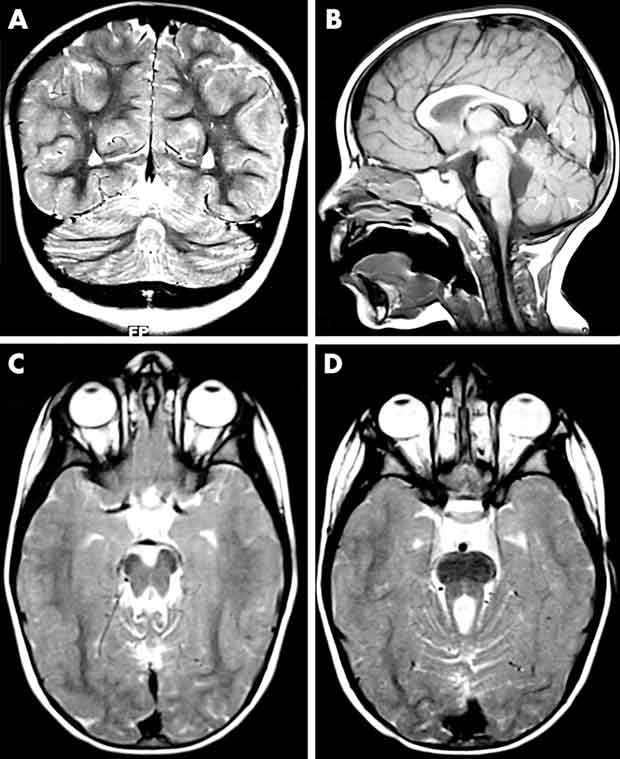

La sindrome di Joubert è un raro disturbo genetico che interessa il verme cerebellare, la parte del cervello che controlla la coordinazione dei muscoli, l’equilibrio e il movimento. Nella sindrome di Joubert, il cervelletto e il tronco encefalico non si sviluppano correttamente e ciò provoca problemi di controllo dei muscoli. Tra gli altri sintomi ci sono problemi al fegato e ai reni, cecità, handicap mentale lieve o moderato e malformazioni ossee come labbro leporino o palatoschisi o polidattilia.